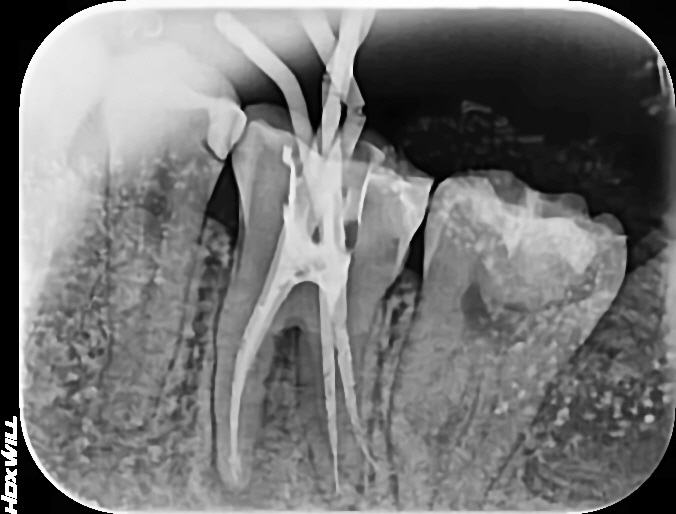

안녕하세요 수서역치과 문정도 치과 수서서울삼성치과 원장 이재현입니다 오늘은 신경치료 후 회복한 환자...